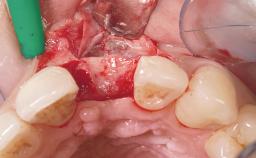

Immediate Placement of an Implant in a Maxillary Left Central Incisor Site

A 33-year-old female patient presented with an upper left central incisor that required extraction after a failed endodontic therapy. The tooth had been traumatized when the patient was a teenager and had undergone several endodontic treatments, including two apicectomy procedures. The patient was in good health and did not smoke. Clinical examination showed that the patient had a high lip line. In full smile, the gingival margins of the upper teeth were visible to the first molars. The gingival margins of central incisors 11 and 21 were only just showing. Examination of tooth 21 confirmed that the tooth was mobile and had hypererupted by 1 mm.

| Soft Tissue Grafting | Simultaneous |

| Bone Volume | Damage to one or more socket walls |